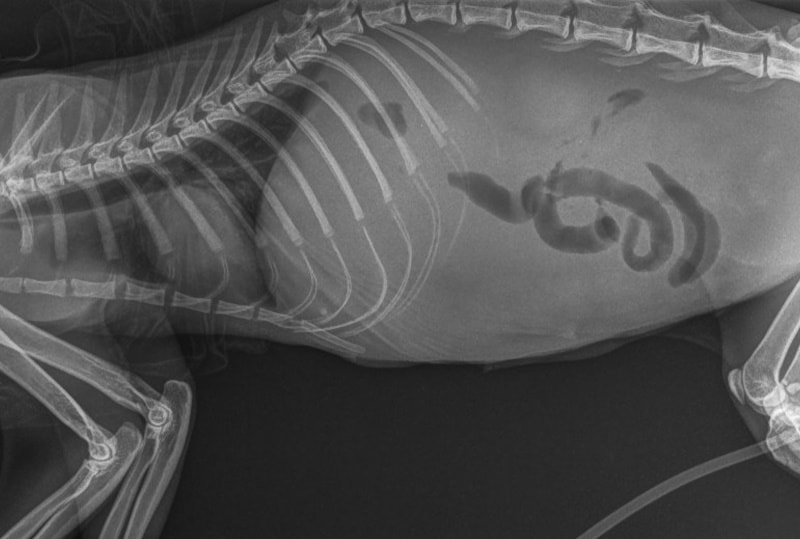

- X-rays

- Ultrasound